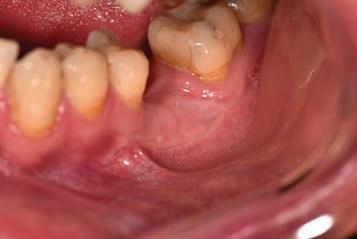

The third step of the treatment consisted of the crown lengthening, necessary to expose an adequate part of the root to obtain, after healing, the correct adhesion of the composite for the pre-prosthetic restoration and the successive prosthetic rehabilitation.

After the surgical flap elevation of the tissue and the bone remodeling, the flap was repositioned apically and sutured with a vertical mattress suture anchored in the periosteum (Figs. 5-6). The suture was removed after 7 days (Fig. 7).

glass fibre Figure 3: Root canal therapy completed under proper isolation. Figure 4: Radiography of completed root canal therapy and reconstruction made completely in glass hybrid cement. Figure 5: Clinical crown lengthening with a minimally invasive technique without mesial and distal discharges. Note the proximity of the reconstruction in glass hybrid material to the mesial bone ridge. Figure 6: Suture at the end of surgical therapy. It was left in place for 7 days Figure 7: Suture removal at 7 days. Post-surgical edema is still present.

Figure 8: Recovery 2 weeks after surgery. Note the disappearance of post-surgical edema. The provisional crown was placed after two weeks to allow the formation of an epithelial-connective seal in the area.